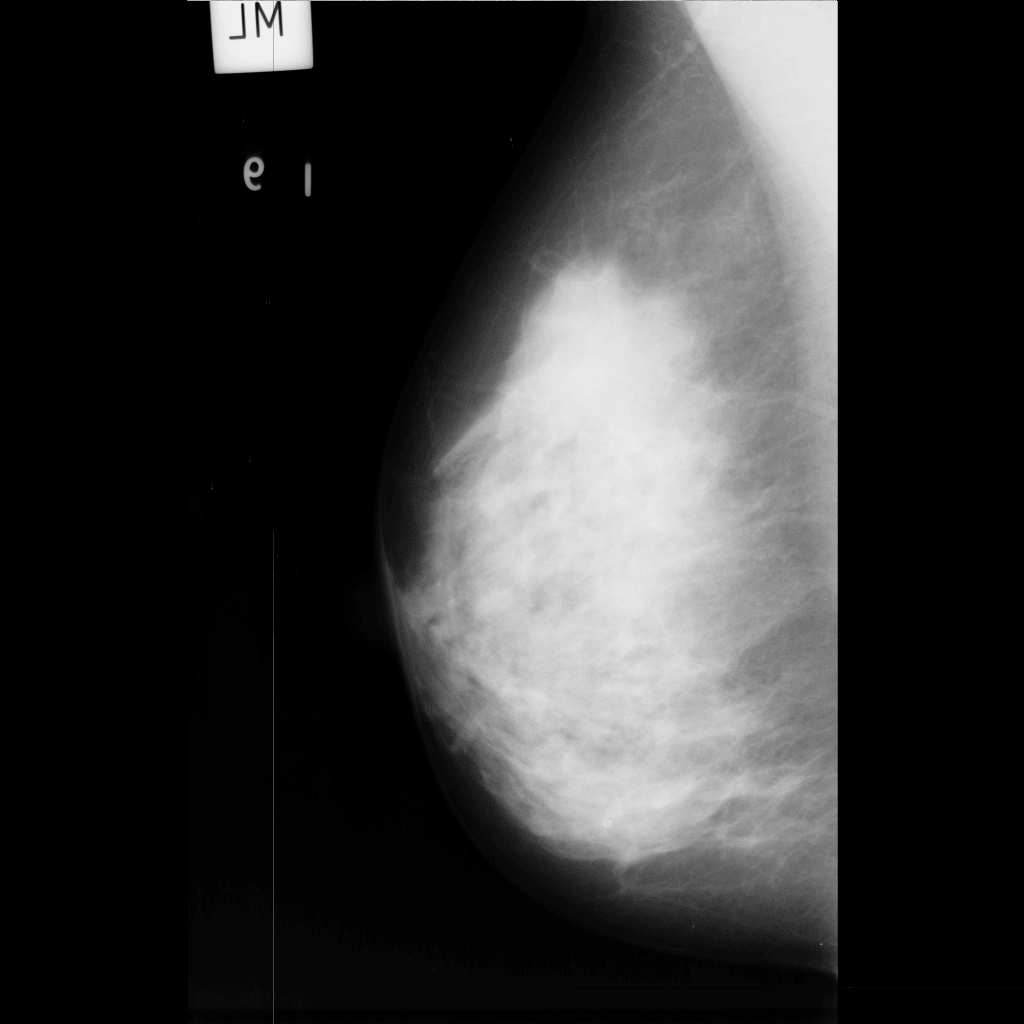

mdb001mdb002mdb003

Output: